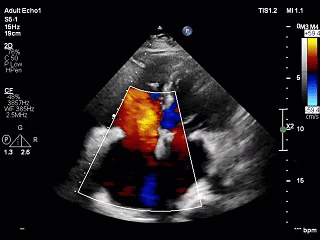

基线评估:超声心动图显示双心房扩大、左心室肥厚、轻度二尖瓣反流、中度三尖瓣反流和中度肺动脉高压(肺动脉收缩压估计为57 mm Hg)。

基线情况:心尖四腔心切面、左心室短轴切面及测量参数

表1 超声心动图数据